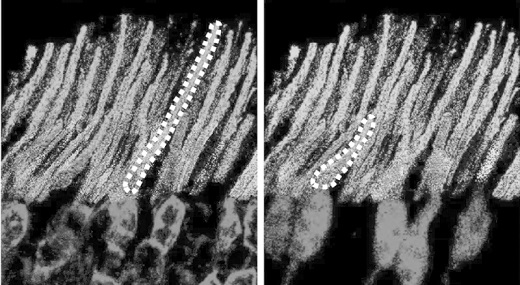

अगला कदम यह था कि नैनोकणों में इस तरह के परिवर्तन किए गए कि वे अवरक्त प्रकाश को नीले की बजाय हरे प्रकाश में तबदील करें। ऐसा इसलिए किया गया क्योंकि जंतुओं के हरे प्रकाश ग्राही नीले की अपेक्षा ज़्यादा संवेदनशील होते हैं। इसके बाद इन नैनोकणों पर एक ऐसे प्रोटीन का आवरण चढ़ाया गया जो प्रकाश ग्राही कोशिकाओं की सतह पर उपस्थित एक शर्करा अणु से जुड़ जाता है। जब ये नैनोकण चूहों के रेटिना के पिछले भाग में इंजेक्ट किए गए तो ये प्रकाश ग्राही कोशिकाओं से जुड़ गए और 10 हफ्तों तक जुड़े रहे। और परिणाम आशा के अनुरूप रहे। चूहों की आंखें अवरक्त प्रकाश के प्रति वैसी ही प्रतिक्रिया देने लगी जैसी वह दृश्य प्रकाश के प्रति देती है। इसके अलावा रेटिना और मस्तिष्क के दृष्टि सम्बंधी हिस्से में विद्युतीय सक्रियता देखी गई। इसके बाद इन चूहों को सामान्य दृष्टि सम्बंधी परीक्षणों से गुज़ारा गया और यह स्पष्ट हो गया कि वे अंधेरे में देख पा रहे थे।